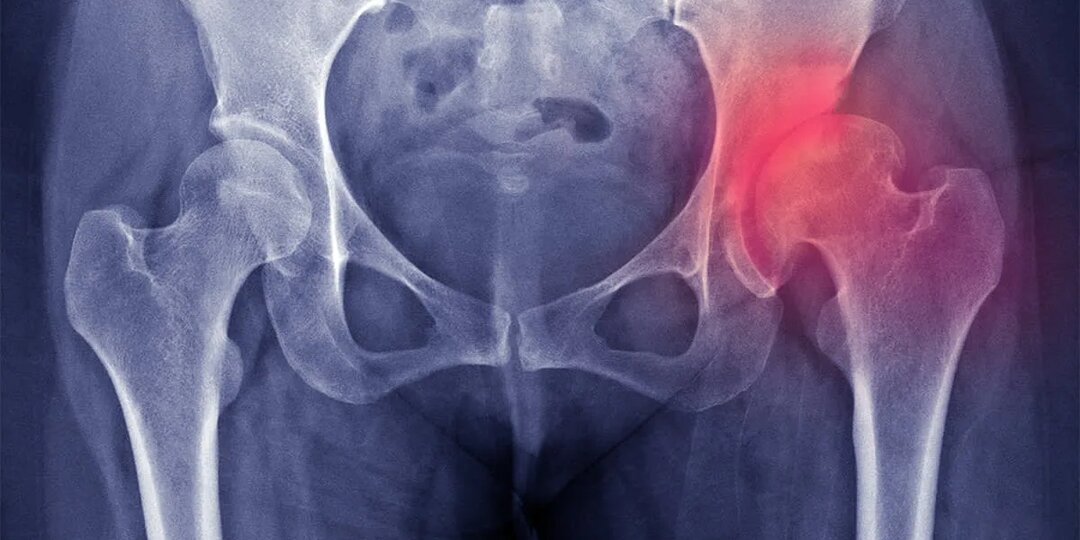

Как победить коксартроз

Если вы чувствуете тупую боль в паху, скованность при первых шагах утром или хруст в тазобедренном суставе при подъёме по лестнице — возможно, речь идёт не просто о «возрастных болях». За этими симптомами часто скрывается коксартроз — дегенеративное заболевание тазобедренного сустава, которое медленно, но уверенно разрушает хрящ и ограничивает подвижность. Многие считают, что коксартроз — это неизбежная часть старения, с которой ничего нельзя сделать, кроме как ждать операции. Но современная наука и клиническая практика показывают: даже при уже начавшихся изменениях можно значительно замедлить прогрессирование болезни, уменьшить боль и сохранить качество жизни — иногда на годы, а то и десятилетия. Главное — действовать осознанно и комплексно. Что такое коксартроз и почему он возникает? Коксартроз — это форма остеоартроза, затрагивающая именно тазобедренный сустав. При этом заболевании постепенно истончается хрящ, который покрывает поверхности сустава и обеспечивает плавное скольжение